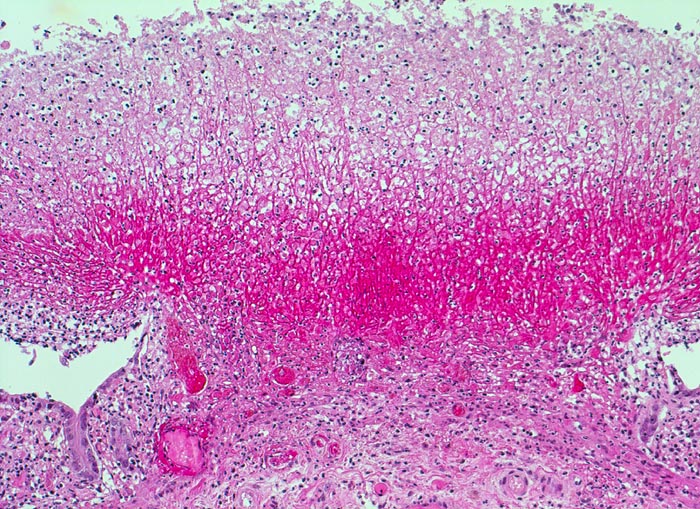

Morphologische Merkmale:

• Herdförmige Schleimhautnekrosen.

• In den Nekrosezonen pilzförmige Pseudomembranen bestehend aus nekrotischem Detritus, Entzündungszellen und Fibrin.

• Zwischen den Pseudomembranen normale Kolonschleimhaut. Das sollte der Kliniker dem Pathologen mitteilen: